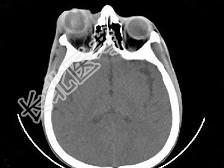

- 单项选择题女,24岁, 发热畏寒数天,右眼睛疼痛, PE:右眼睑肿胀, 结膜充血,伴右眼突出, CT如图所示,最可能的诊断是 ( )